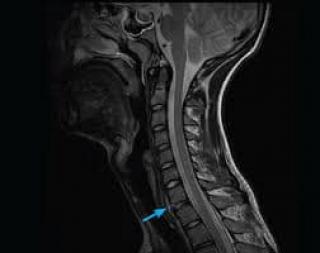

Для точной диагностики грыжи шеи пациенту необходимо сделать МРТ шейного отдела позвоночника и с его результатами прийти на консультацию к неврологу или вертебрологу. Выглядеть на МРТ грыжа шейного отдела позвоночника будет как заметное выбухание в области межпозвоночных дисков.

Как выглядит грыжа на МРТ

| МРТ снимок - грыжа поясничного отдела позвоночника | МРТ снимок - грыжа шейного отдела позвоночника | МРТ снимок - грыжа грудного отдела позвоночника |

![]() | ![]() | ![]() |